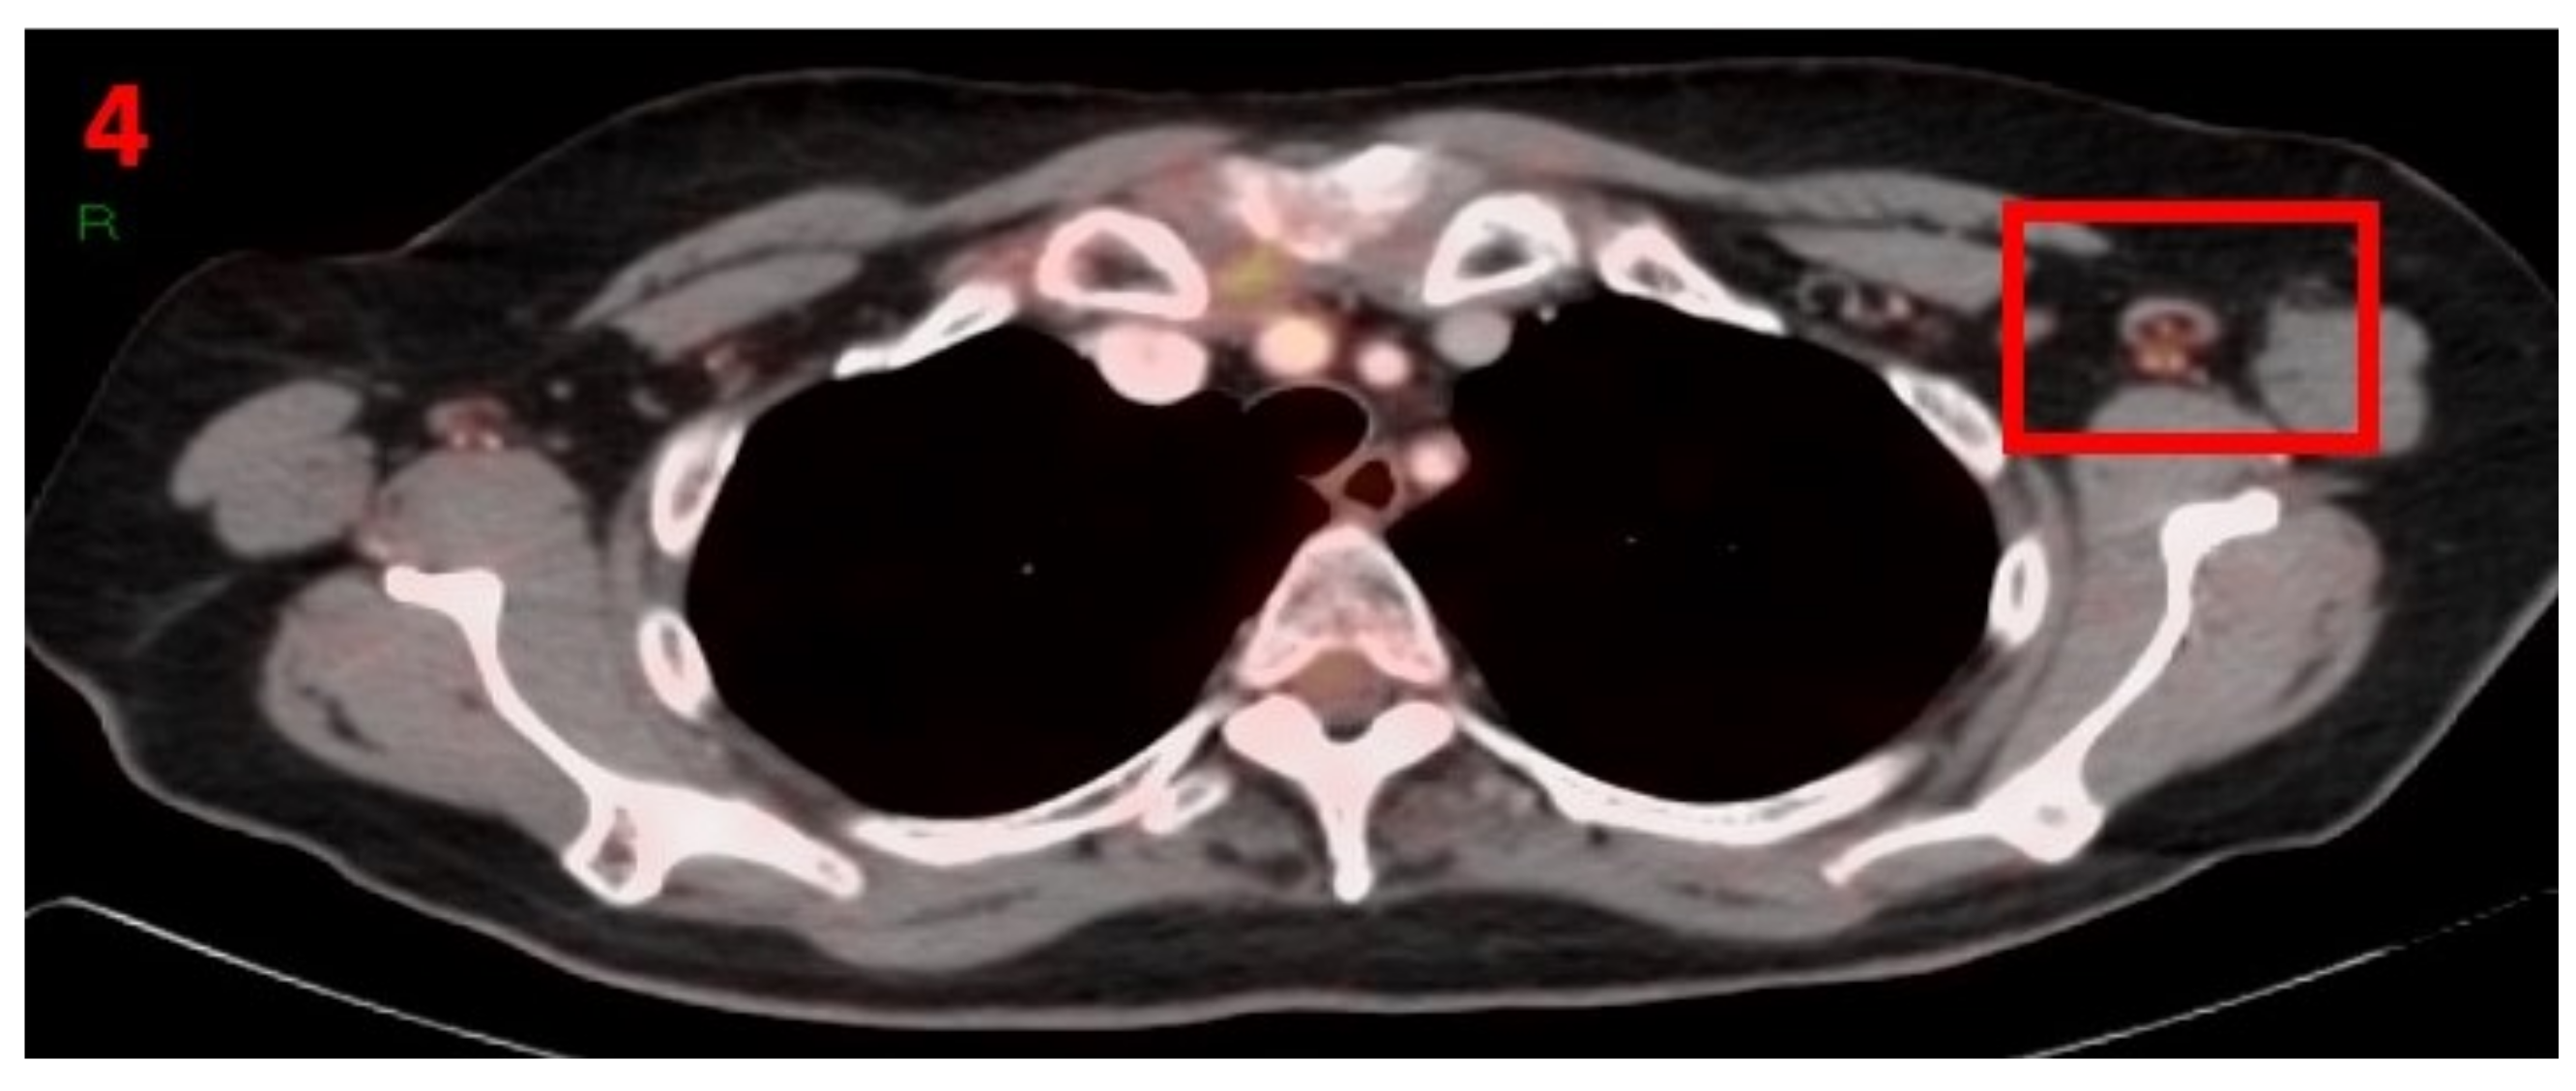

3.4. Case No 4

| Case no.4 | Scc of skin | Left arm | 10 days | Hypermetabolic uptake in the left axillary region and lymphadenopathy | First vaccine | 9 mm | 4.2 | Pfizer-BioNTech |